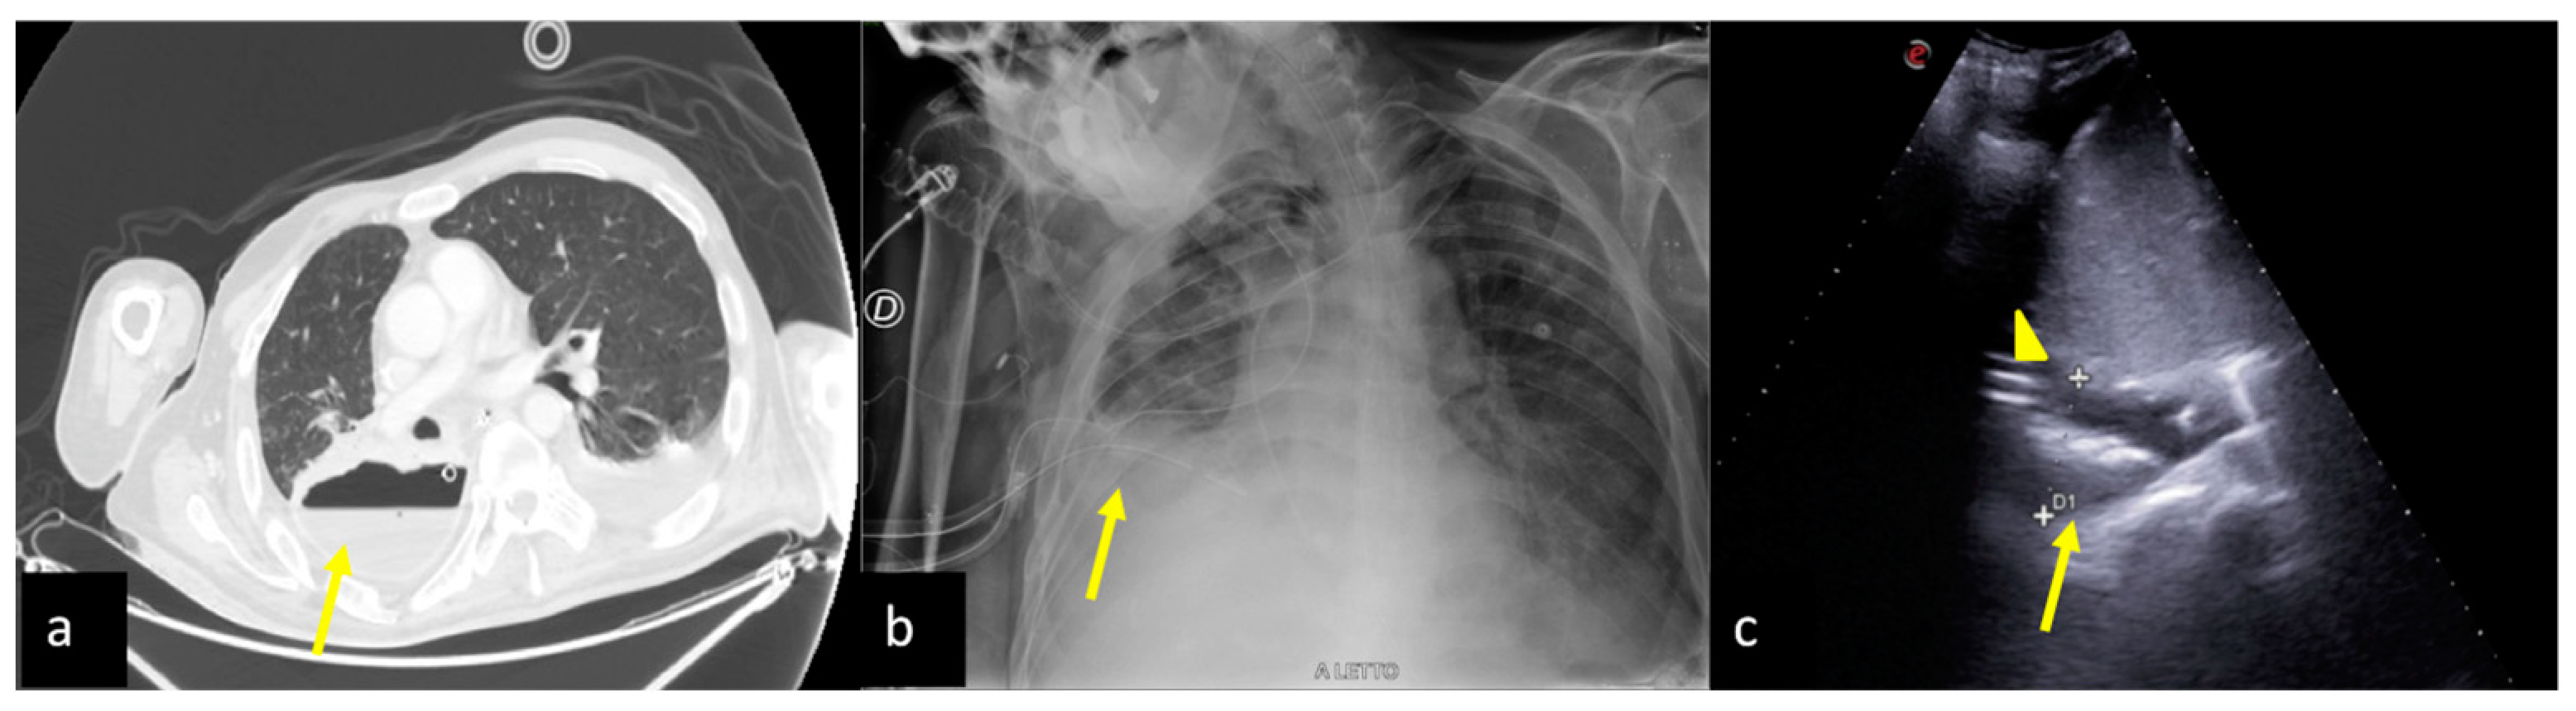

2.6. Pulmonary Contusion

3. Confirming or Excluding Pneumothorax and Monitoring its Evolution